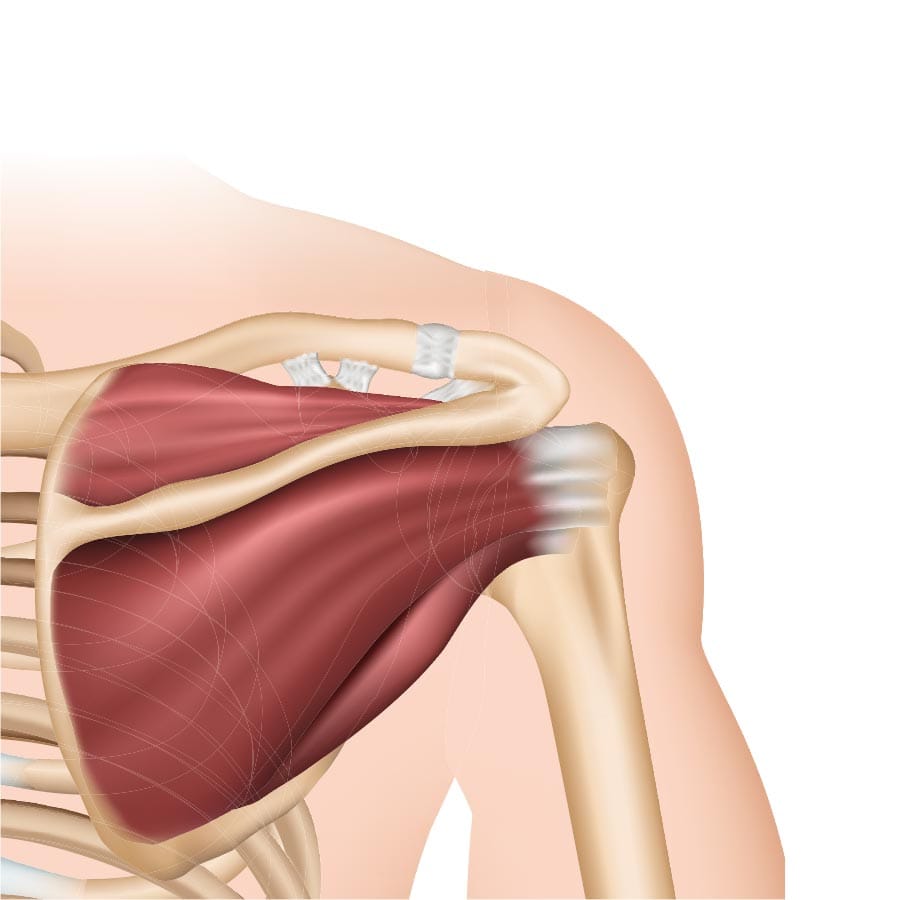

تعتبر أوتار الكتف الدوارة من أهم المكونات التشريحية في جسم الإنسان، فهي تساهم في استقرار مفصل الكتف وتسمح بتحريك الذراع في جميع الاتجاهات، وتشمل هذه الأوتار العضلات الأربعة الأساسية: العضلة فوق الشوكة (Supraspinatus)، العضلة تحت الشوكة (Infraspinatus)، العضلة المدورة الصغيرة (Teres Minor)، والعضلة تحت الكتف (Subscapularis)، وهذه الأوتار تعمل بتناسق تام للحفاظ على قوة ومرونة الكتف، ومع ذلك فهي معرضة للإصابة بعدة مشاكل، ومن أهمها اختناق الأوتار الدوارة وهو ما يمكن أن يؤدي على المدى الطويل إلى تمزق جزئي أو كامل للأوتار، وهذا الأمر يؤثر بشكل مباشر على وظيفة الكتف والحياة اليومية للمصاب؛ وخلال السطور القادمة سنقوم بشرح كافة التفاصيل التي تخص سؤال هل اختناق الاوتار الدوارة يؤدي الي القطع ؟ والتعرف علي أفضل دكتور لعلاج اوتار الكتف.

اختناق الأوتار الدوارة Rotator Cuff Impingement يحدث عندما تضغط العظام المحيطة بالكتف على الأوتار أثناء تحريك الذراع، خصوصًا عند رفع الذراع إلى الأعلى أو تحريكها جانبًا ويعد هذا الاحتكاك سببًا رئيسيًا لالتهاب الأوتار وقد يتفاقم مع التقدم في العمر أو مع الإفراط في استخدام الكتف في الرياضات التي تتطلب حركات متكررة فوق مستوى الرأس، ويصاحب الاختناق عادة شعور بالألم أثناء الحركة، ضعف في الكتف، وأحيانًا الطقطقة أو الاحتكاك، وإذا استمر الاختناق لفترات طويلة، فإنه يؤدي إلى تآكل الألياف وتضعف الأوتار تدريجيًا وهو ما يمهد الطريق لتمزق الأوتار الدوارة.

يعد الاختناق المزمن للأوتار الدوارة من العوامل الرئيسة المؤدية إلى تمزق جزئي أو كامل للأوتار، فالتعرض المستمر للاحتكاك يضعف ألياف الأوتار تدريجيًا، وتظهر الدراسات الطبية أن الأشخاص الذين يعانون من اختناق الأوتار لفترات طويلة دون علاج يواجهون خطر تمزق بنسبة تتراوح بين 30% و50% على المدى الطويل، وغالبًا ما يكون التمزق في أوتار العضلة فوق الشوكة (Supraspinatus) لأنها تقع مباشرة تحت منطقة الضغط، ويبدأ التمزق عادة كتمزق صغير جزئي ثم يتطور تدريجيًا إلى قطع كامل، مما يقلل قدرة الكتف على رفع الذراع وحمل الأوزان، ويصاحبه الألم المستمر وضعف العضلات.